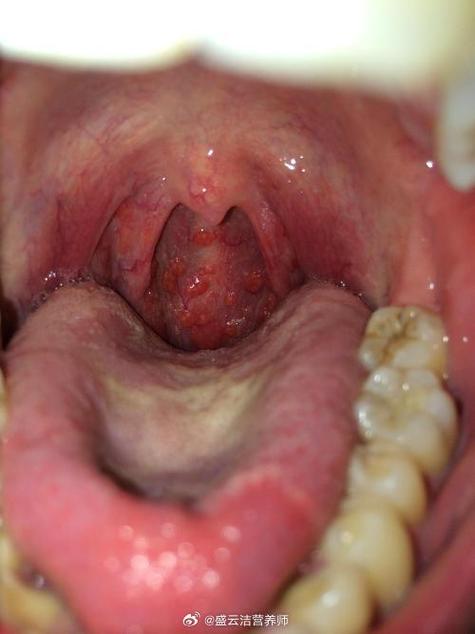

- 慢性咽炎:长期的炎症会导致咽后壁淋巴滤泡增生,看起来像有小颗粒,让人感觉有东西。

- 扁桃体炎/扁桃体结石:扁桃体上的小结石或隐窝里的食物残渣,会让人感觉有异物。